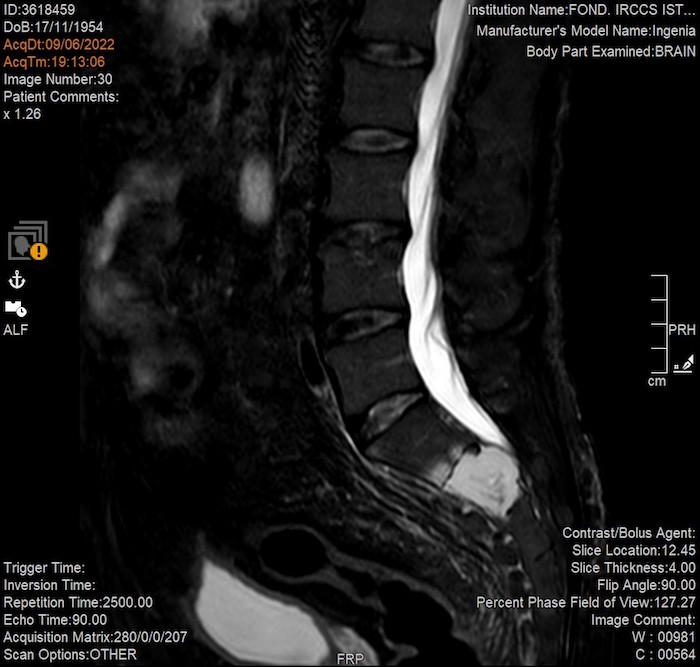

MZ: Esiste probabilmente un punto di rottura tra la necessità del referto e lo stupore della forma. In risonanza, i parametri T1, T2 o le sequenze pesate in diffusione cambiano radicalmente il contrasto e l’aspetto dei tessuti. Un artista può utilizzare questi “strumenti di contrasto” come se fossero filtri pittorici (o qualcosa del genere) e cosa può trovare o individuare nelle immagini registrate durante una risonanza magnetica?

DS: Certamente le scelte tecniche (immagini pesate in T1 o T2 o immagini in tecnica di diffusione) rispondono in momenti diversi dello stesso esame alla richiesta di risoluzione spaziale e risoluzione di contrasto. “Filtri pittorici” finalizzati direi. Detto questo direi che esiste un continuum senza soluzione fra estetica e finalità clinica. Anche in questo senso la medicina è un’arte, l’arte della cura, la cui via l’artista (in questo caso il medico) va cercando nelle immagini che con il tecnico e la macchina produce.

MZ: Il ritmo della RM potrebbe ricondurre in qualche modo a qualcosa che è simile alla sintesi granulare o il glitch. Hai mai trovato una corrispondenza visiva tra la “grana” dell’immagine prodotta e la frequenza acustica della sequenza (per esempio il passaggio tra un’eco di spin e una sequenza ultraveloce)?

DS: Esiste una precisa correlazione fra la tipologia di suono e la tipologia (sequenza, in gergo tecnico) di immagine. In linea di massima, in una data apparecchiatura, più veloce è la sequenza e maggiore sarà il “rumore” (in senso ottico) dell’immagine. Quindi risponderei dicendo che la granulosità è determinata dalla necessità di ottenere le immagini in un dato lasso di tempo (quante similitudini con la fotografia, sto pensando).